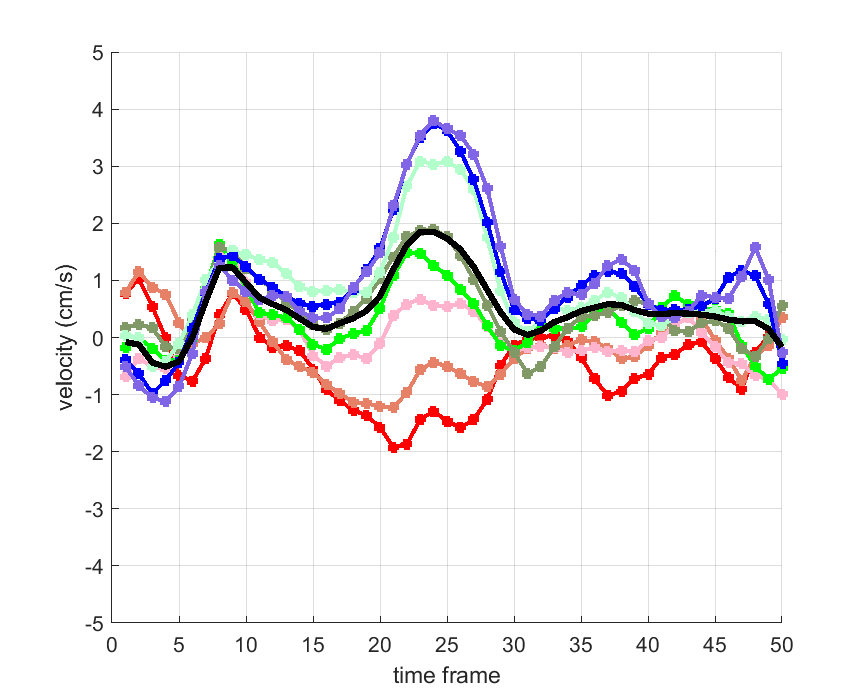

Time courses of the estimated translational component per subject, frame, slice and volume along the 3 velocity directions x, y and z are presented in Fig.6 - Fig.8.